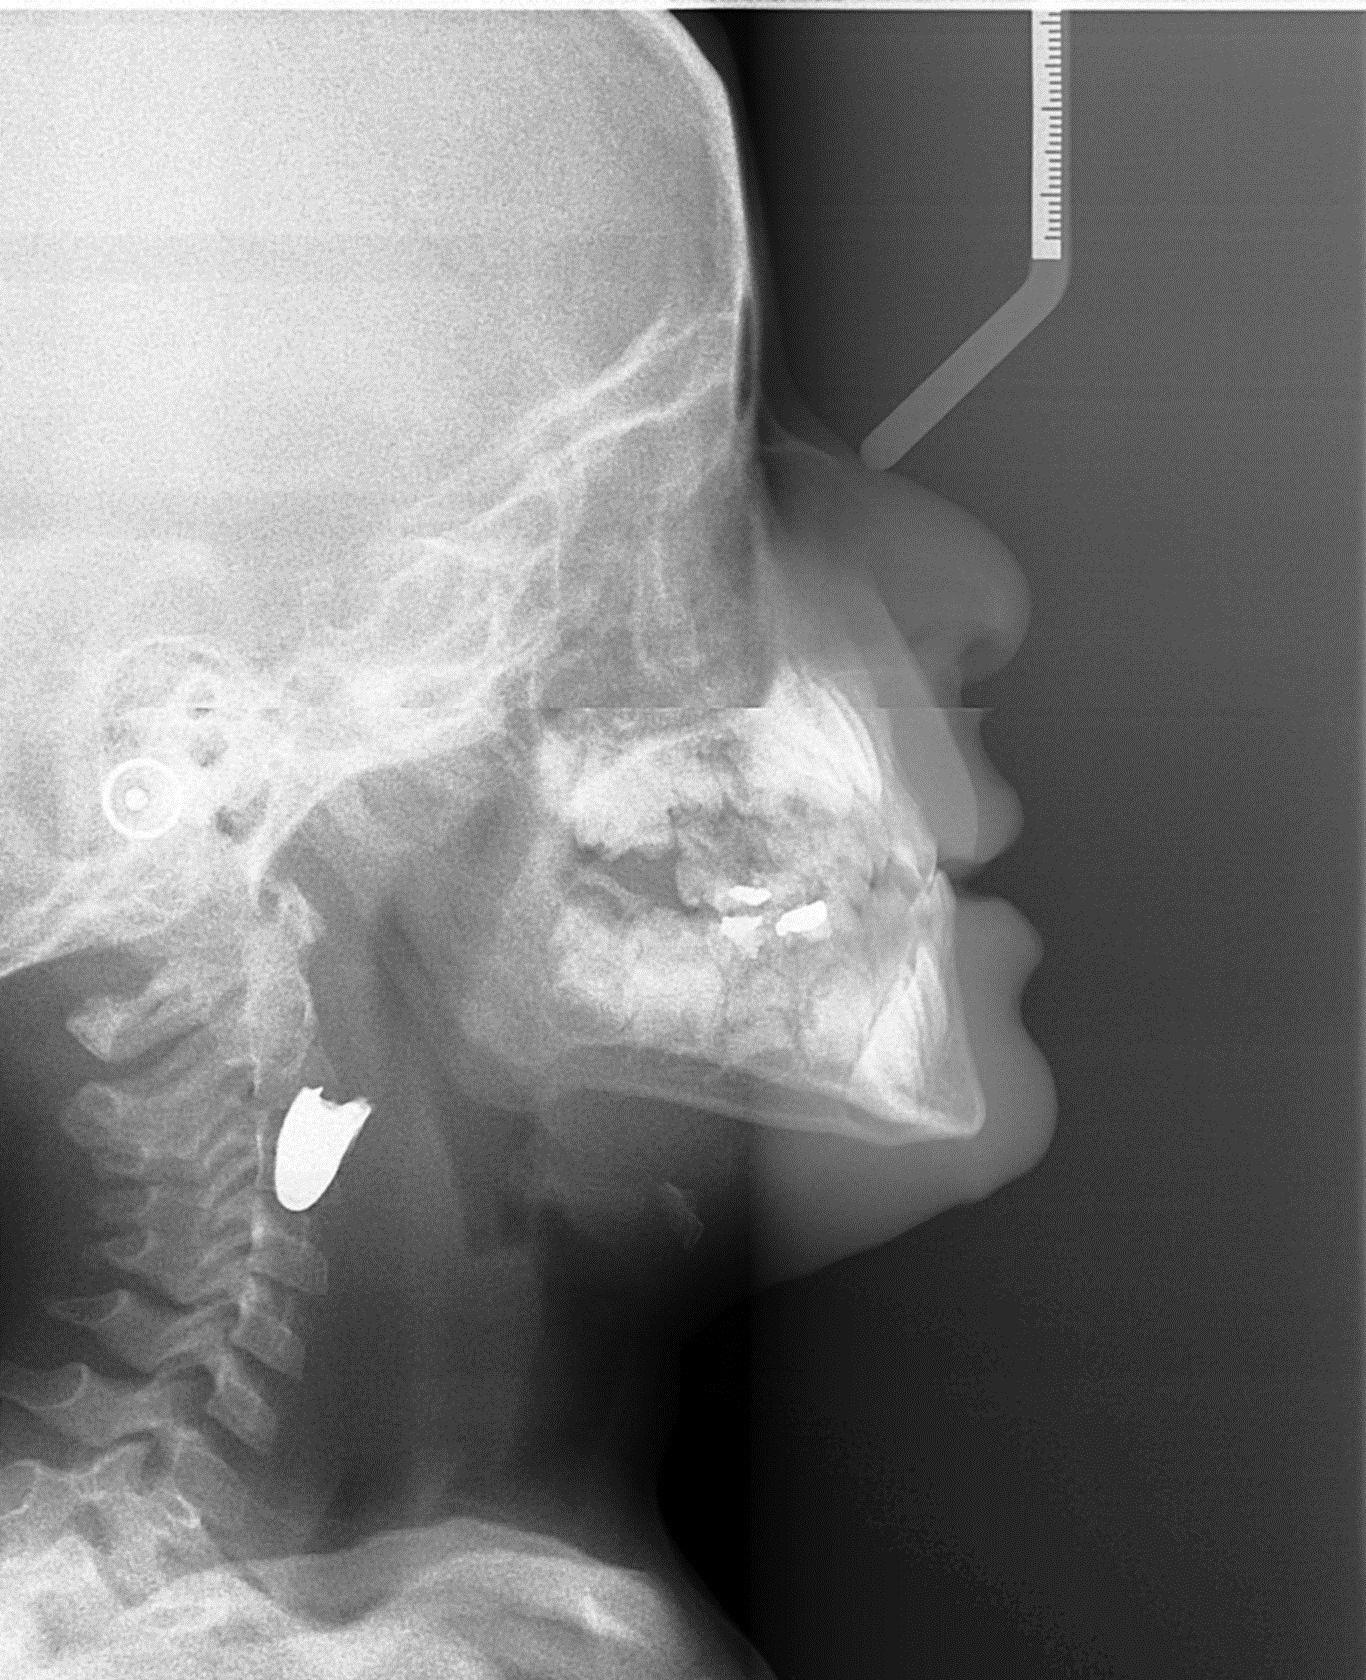

לפני כשבוע נקלע הילד עם אביו לחילופי אש ולאחר שנפגע פונה בדחיפות למעבר הגבול. עם הגיעו אתמול (ג') לבית החולים רמב"ם בחיפה, בוצעו בדיקות דימות בילד כדי לאתר את מיקומו המדויק של הקליע, שהציגו תמונה עגומה. הקליע, שירד לכיוון צווארו של הילד, עבר את הלוע והלשון, נתקע במיקום מסוכן במיוחד: צמוד לעורקי וורידי הצוואר, מרחק של חמישה מילימטרים מעורק התרדמה (קורוטיס), המוביל דם למוח ובצמוד לווריד הג'וגולרי בצוואר. במצב כזה הקליע יכול היה לגרום לפגיעה באספקת הדם למוח או בעצבי עמוד השדרה, ולהוביל לנזק מוחי, לנכות קשה או למותו של הילד.